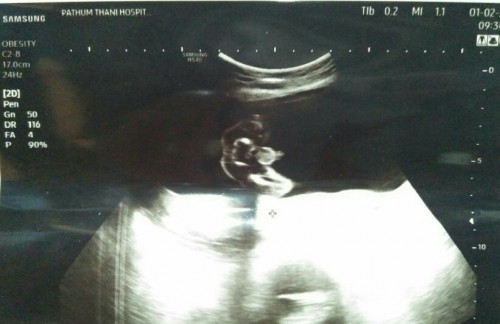

หมอบอกว่าผู้ชาย แต่บอกครั้งหน้าจะคอนเฟิร์ม แม่ๆช่วยดูหน่อยจ้า😬

ไข่น้องชัดเลยค่ะแม่

ชายชัดเลยค่ะ

น้องมีไข่😂